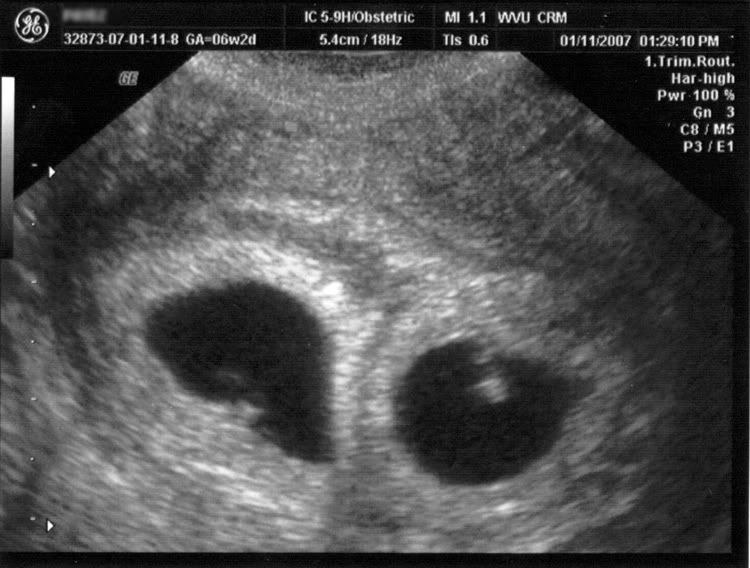

First Trimester Abnormalities On Ultrasound

First Trimester of Pregnancy Elizabeth Lipson, HMS III. First Trimester Sonography • Localization of Gestational Sac • • persistent cramps and bleeding, abortion in in progress, os open • appearance varies depending on retained products present – ... Get Content Here